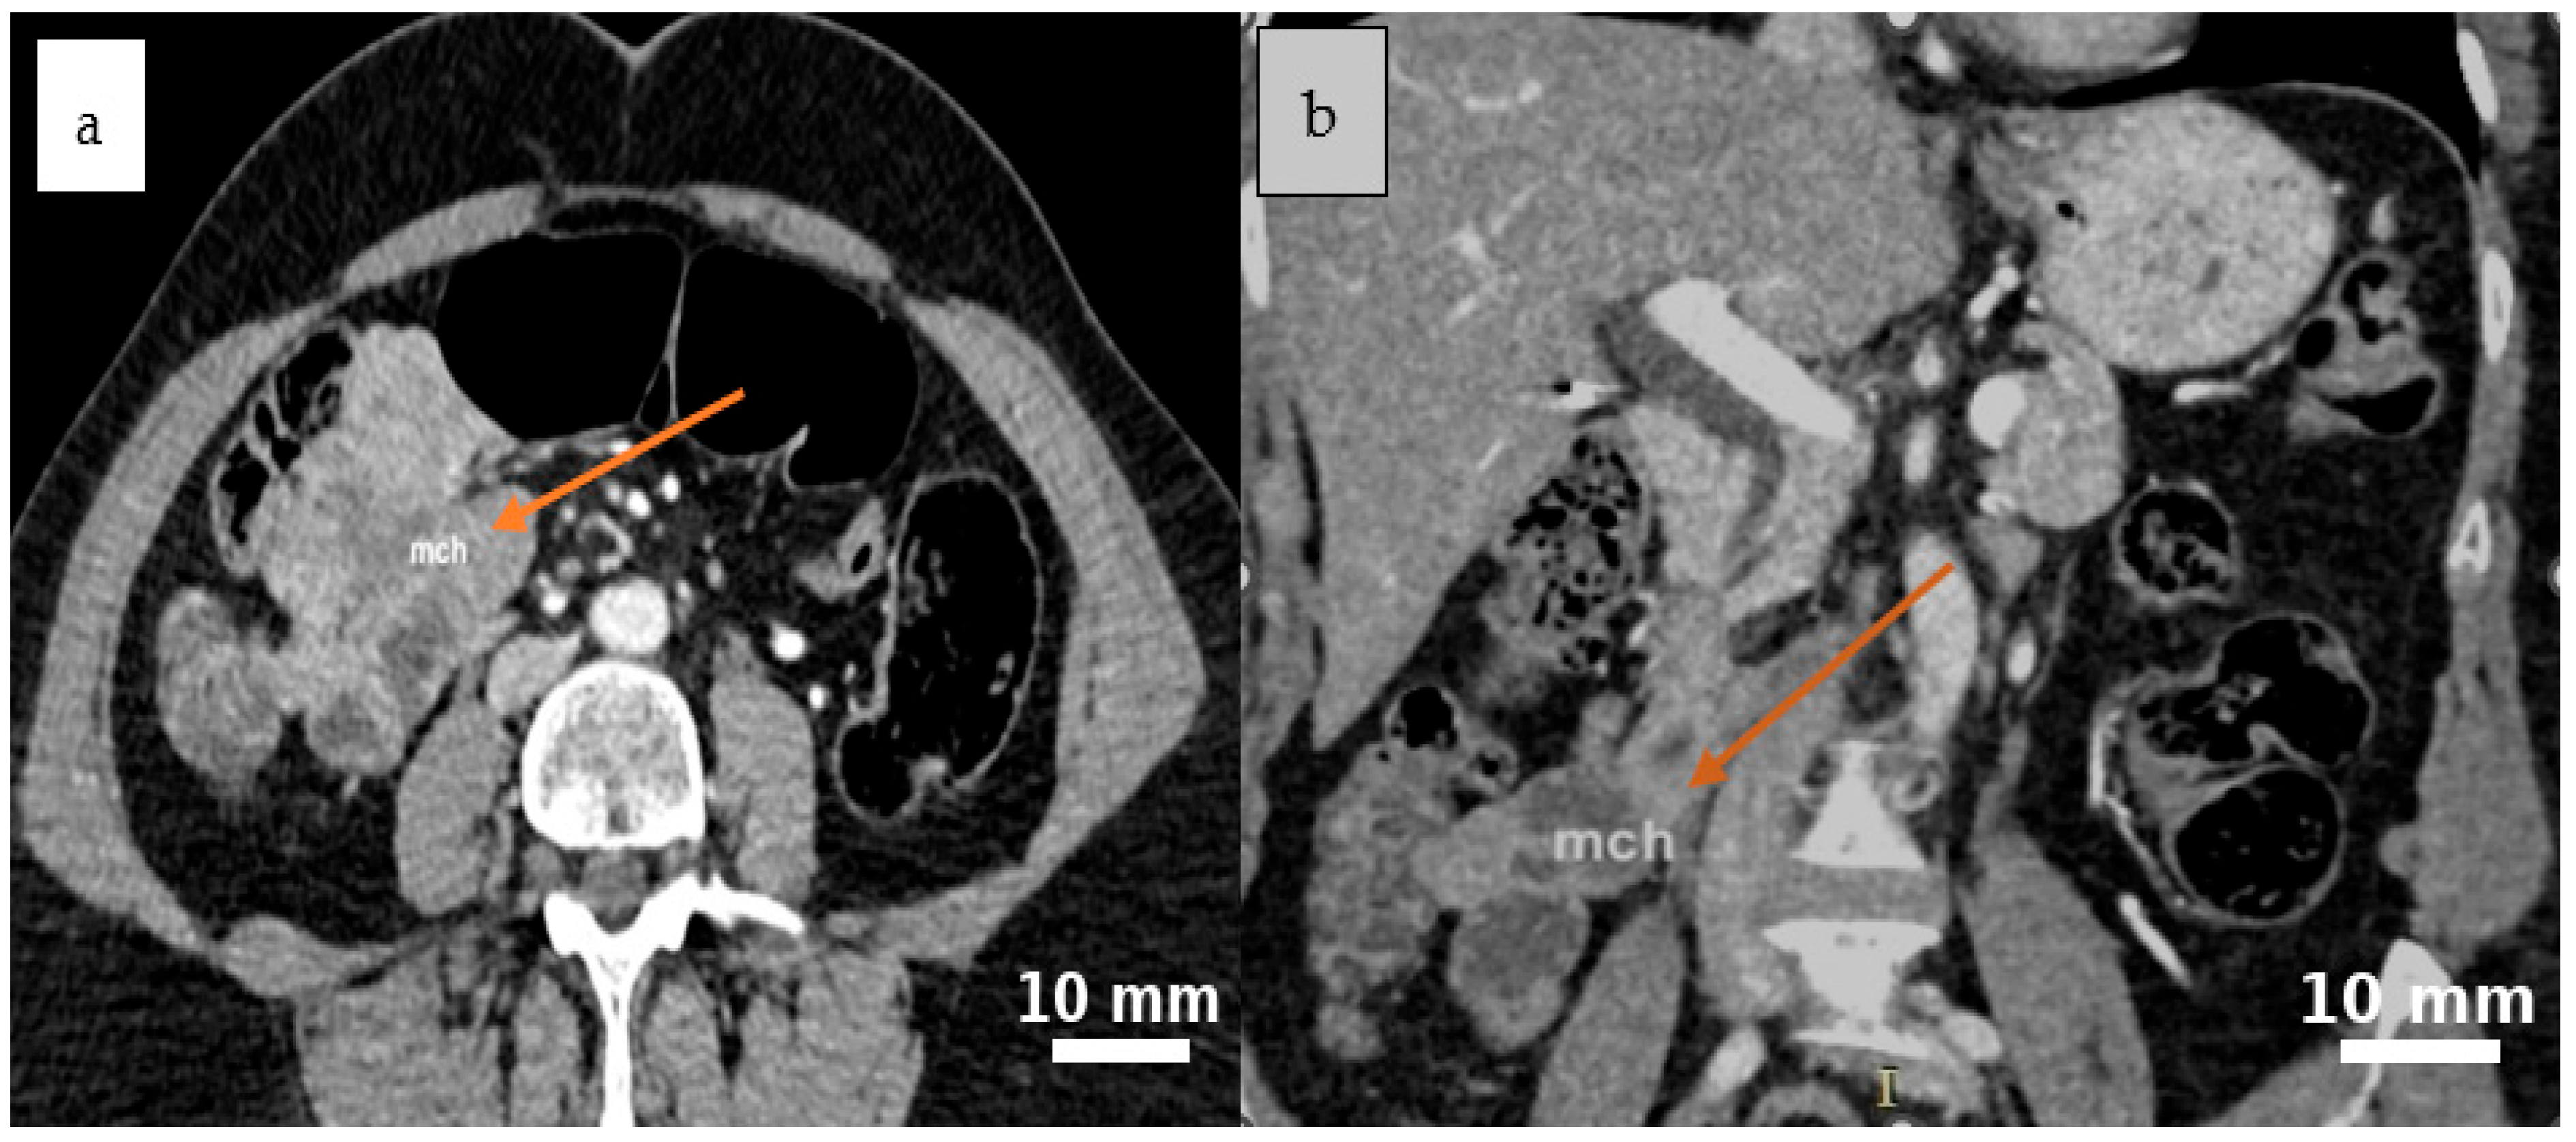

2.4. Diagnostic Assessment

3.2. Clinical and Imaging Features

3.2.3. Role and Limitations of Imaging